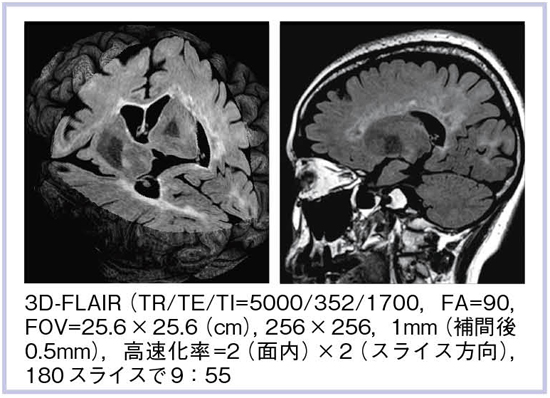

次世代のOpen Bore 3T MRIによる臨床応用 3T MRIの臨床応用。Look back Gyro cup ②「 CSF Flow with Low RFA SSTSE。次世代のOpen Bore 3T MRIによる臨床応用 3T MRIの臨床応用。